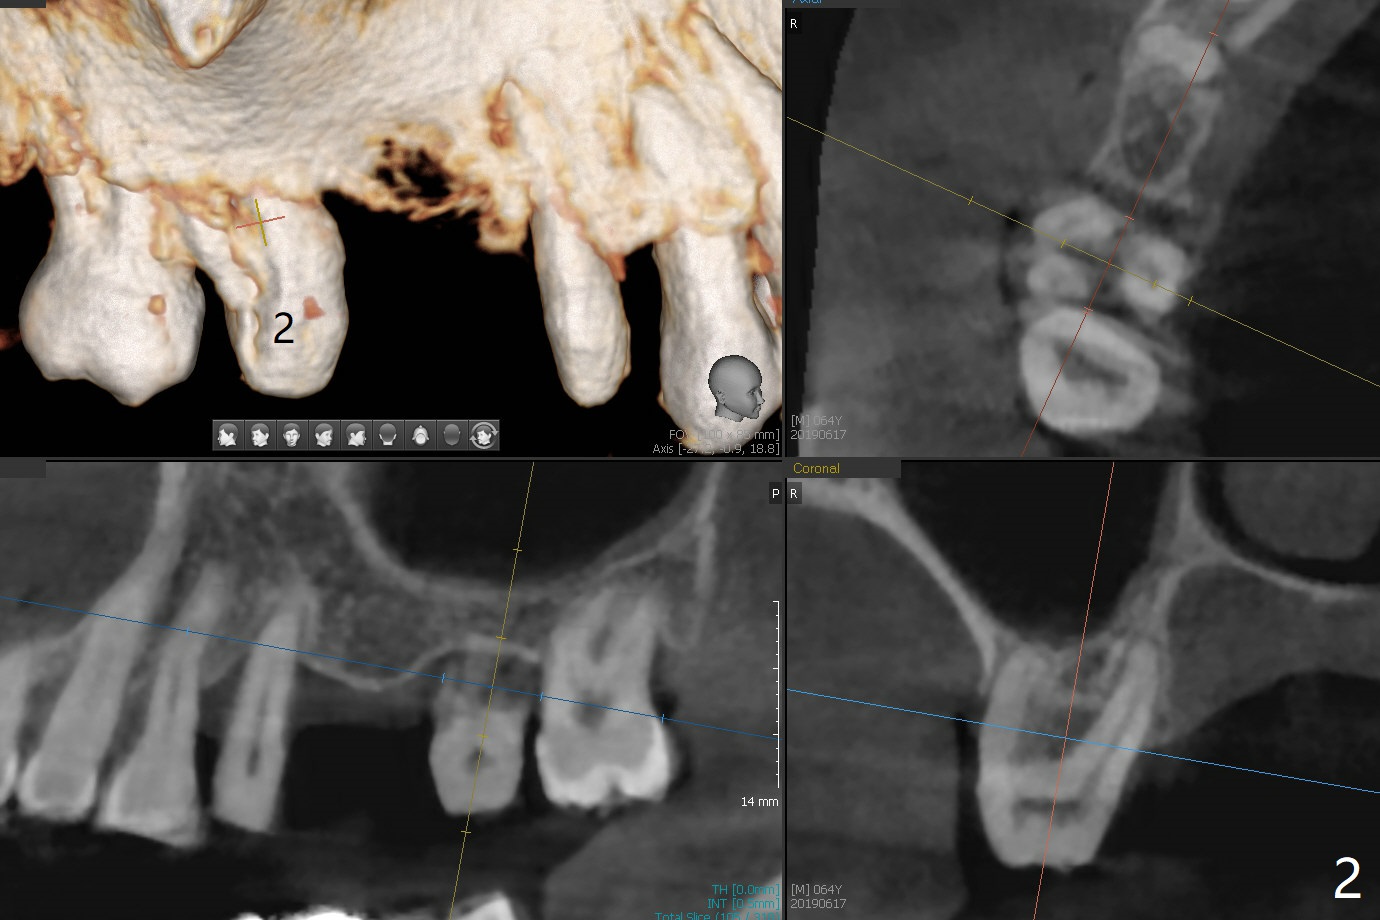

A 64-year-old man has a loose FPD at #2-4. After discussion, he agrees to have it removed for implant at #3 (Fig.1). In fact the bone loss at #2 is severe (Fig.2, as compared to #4 (Fig.3)). When the implant osteointegrates (Fig.4), make single unit crowns and let the patient decide whether the tooth #2 is salvageable or not.